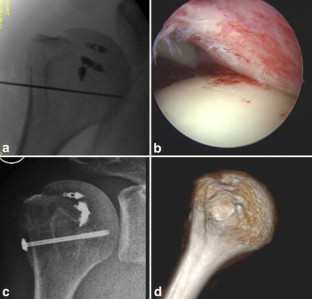

Combined fractures of the greater and the lesser tuberosity are very rare injuries. This is a case report on arthroscopic treatment using suture anchors and one distal fixation screw. Clinical and radiographic follow-up showed recovery of active motion and consolidation of the fragments in anatomic positions. Level of evidence V.

Fig. 1

Fig. 2

Fig. 3